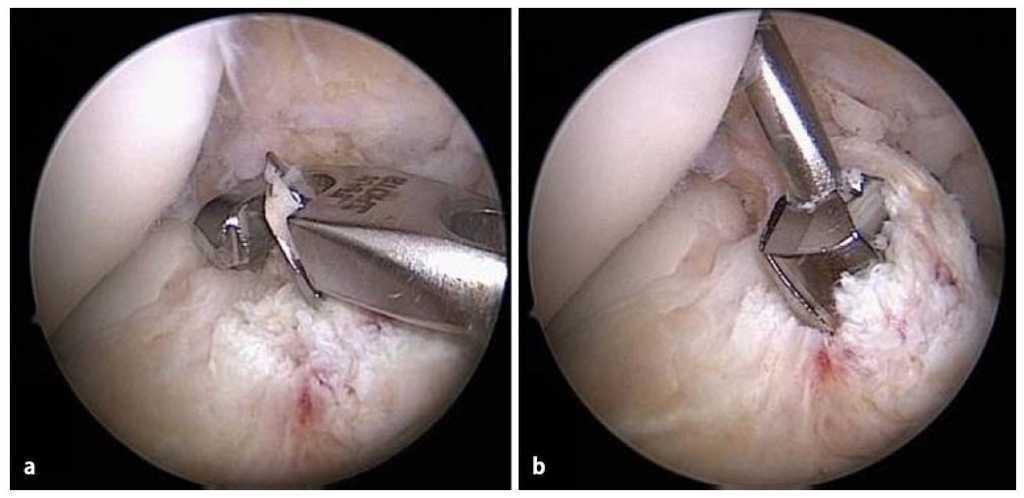

Fig. 12 La guía (a) se introduce en toda su longitud perforando con la broca más delgada (diámetro 4,5 mm) (b). A continuación se mide la longitud del túnel con un medidor de profundidad especial (c). La longitud del túnel varía entre 30 y 45 mm.

Fig. 13 Después de determinar la longitud del túnel se vuelve a insertar la guía dentro del túnel y se ensancha paso a paso a lo largo de los 30 mm distales, hasta conseguir el diámetro del injerto (a). A modo alternativo, también se puede dilatar el túnel con dilatadores femorales (b). Durante el proceso de dilatación, el hueso se comprime en la zona de la pared del túnel. Durante la perforación pueden producirse defectos óseos.

Fig. 14 Representación esquemática del túnel femoral. a Longitud de túnel total. b Longitud del orificio ciego. c Medidor de profundidad.

Fig. 15 a) La imagen muestra la posición del túnel femoral en el centro de la inserción femoral. b) A través del portal medial se controla la posición del túnel femoral. Línea punteada negra: interfaz hueso-cartílago; línea punteada blanca: línea intercondílea; línea punteada roja: inserción del LCA; línea punteada azul: interfaz hueso-cartílago. AM: inserción del haz AM; PL: inserción del haz PL.